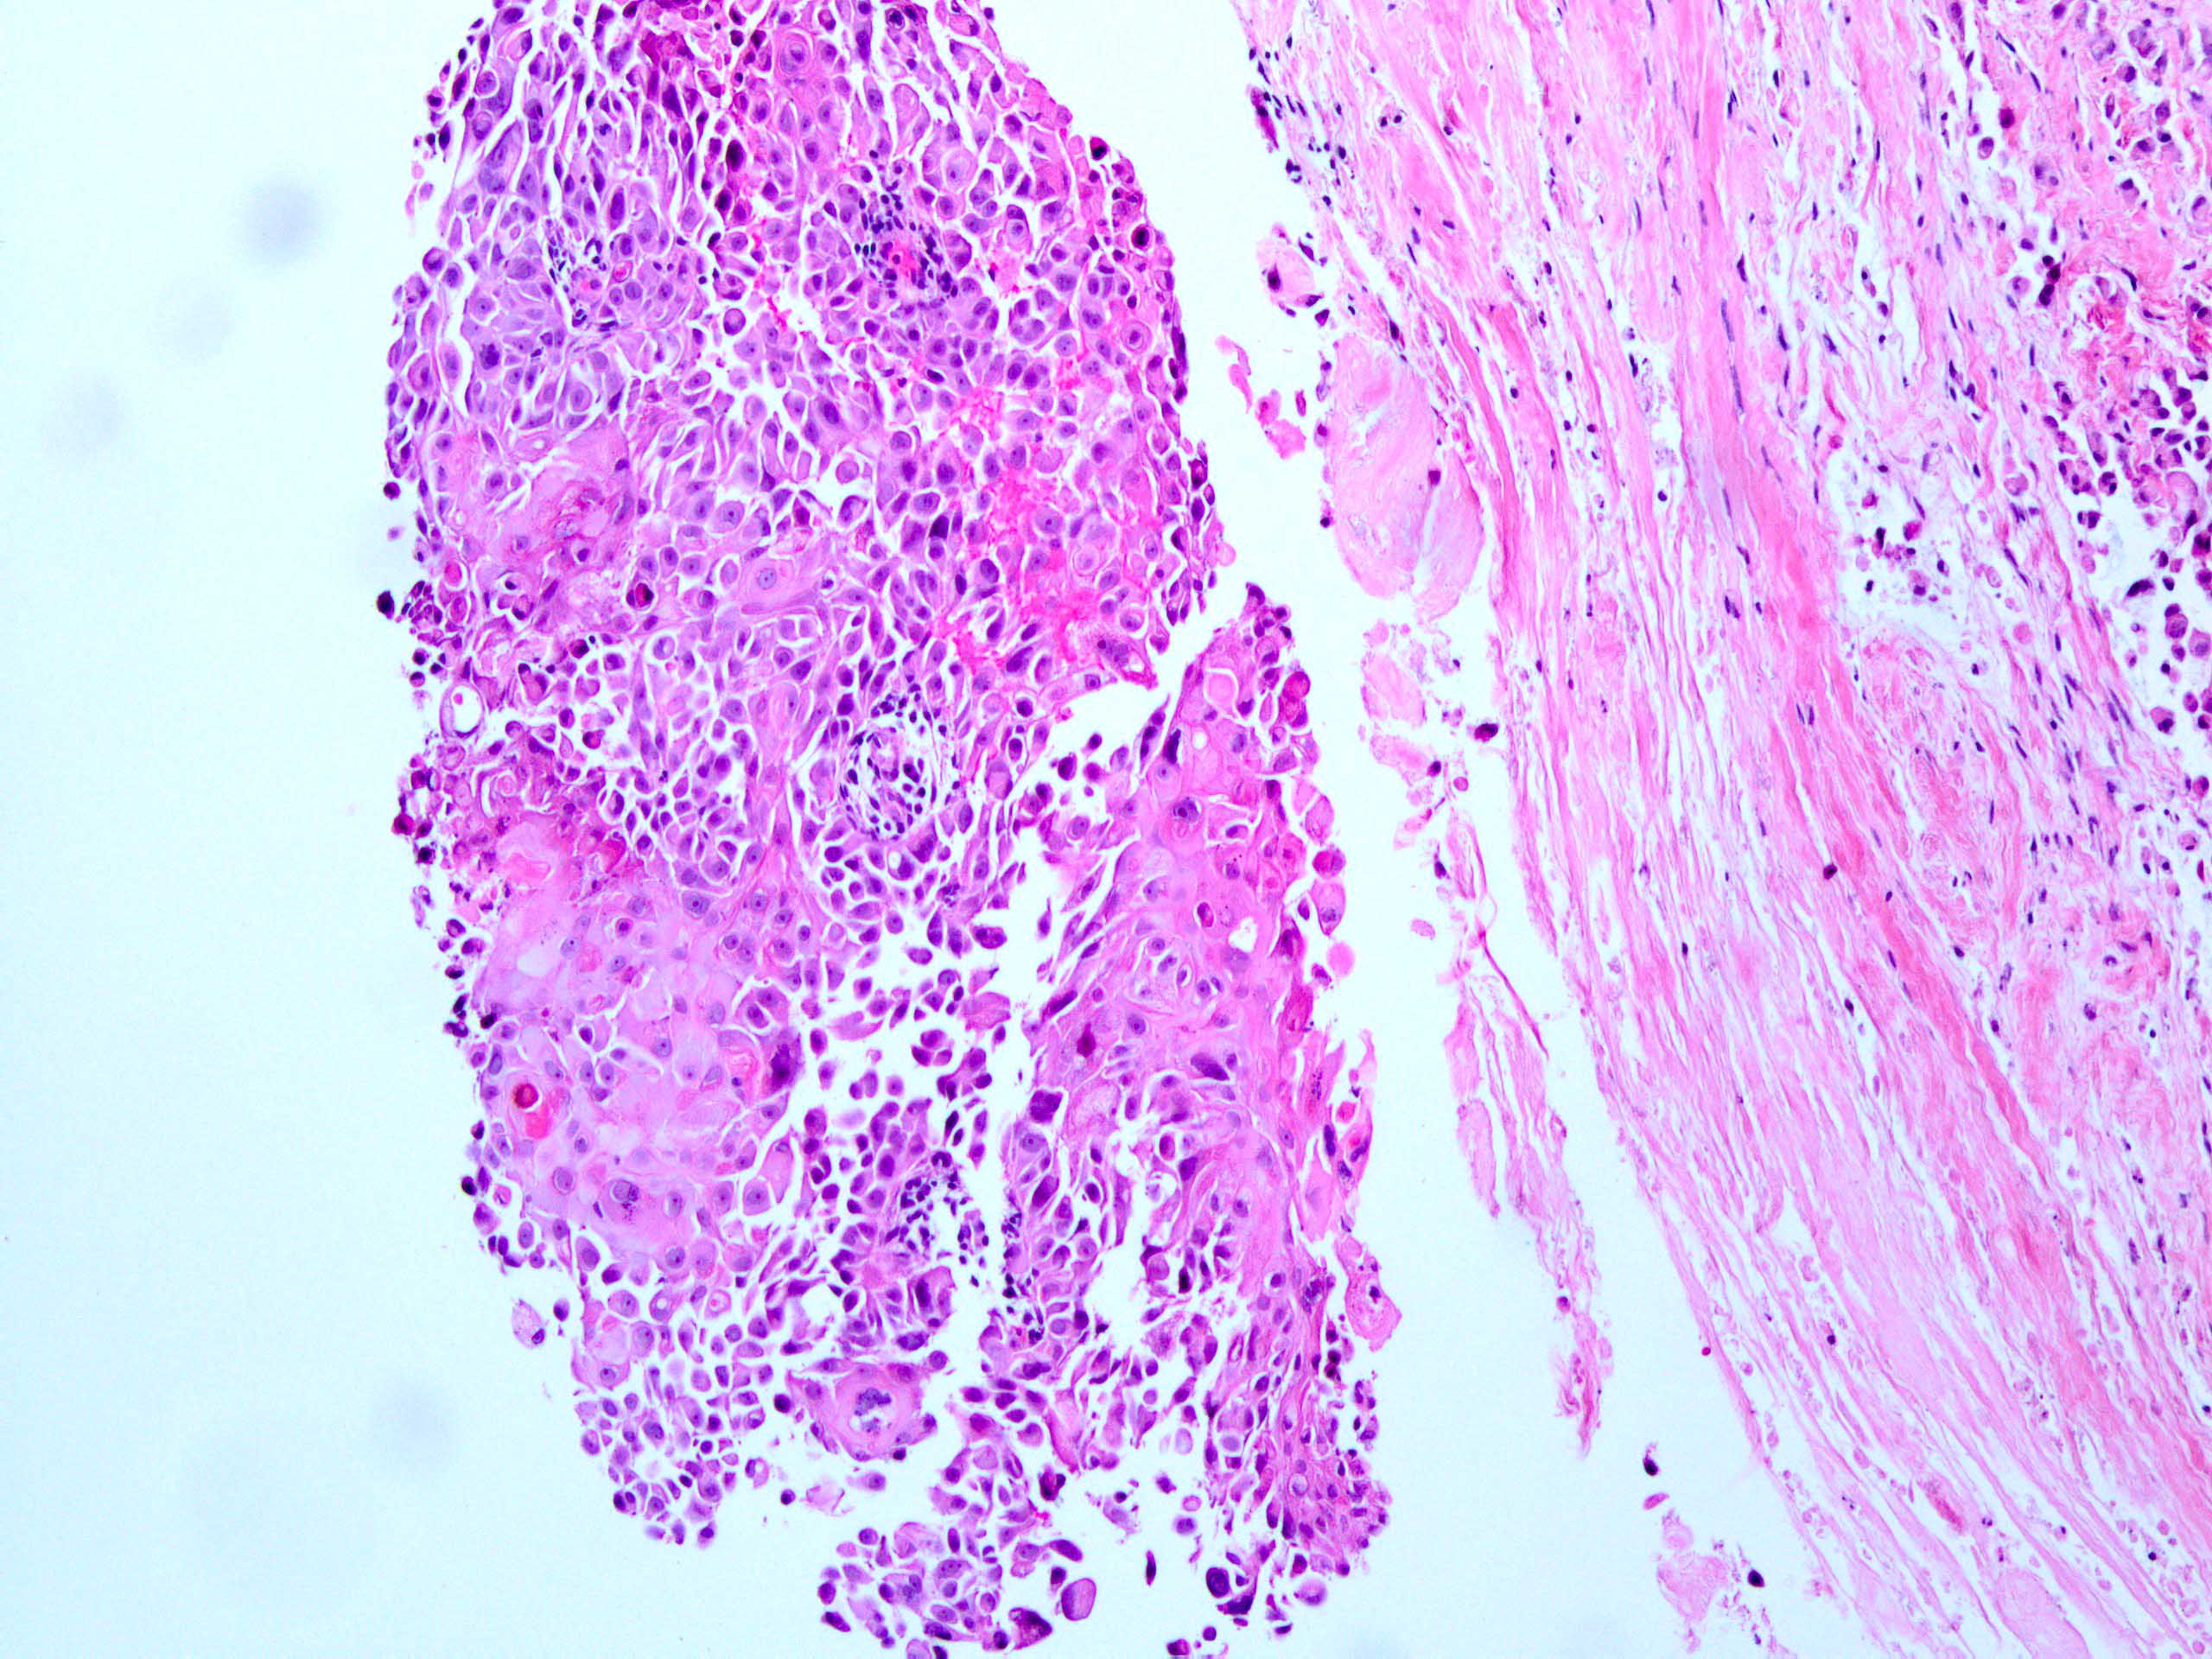

metaplastic breast cancer pathology outlines